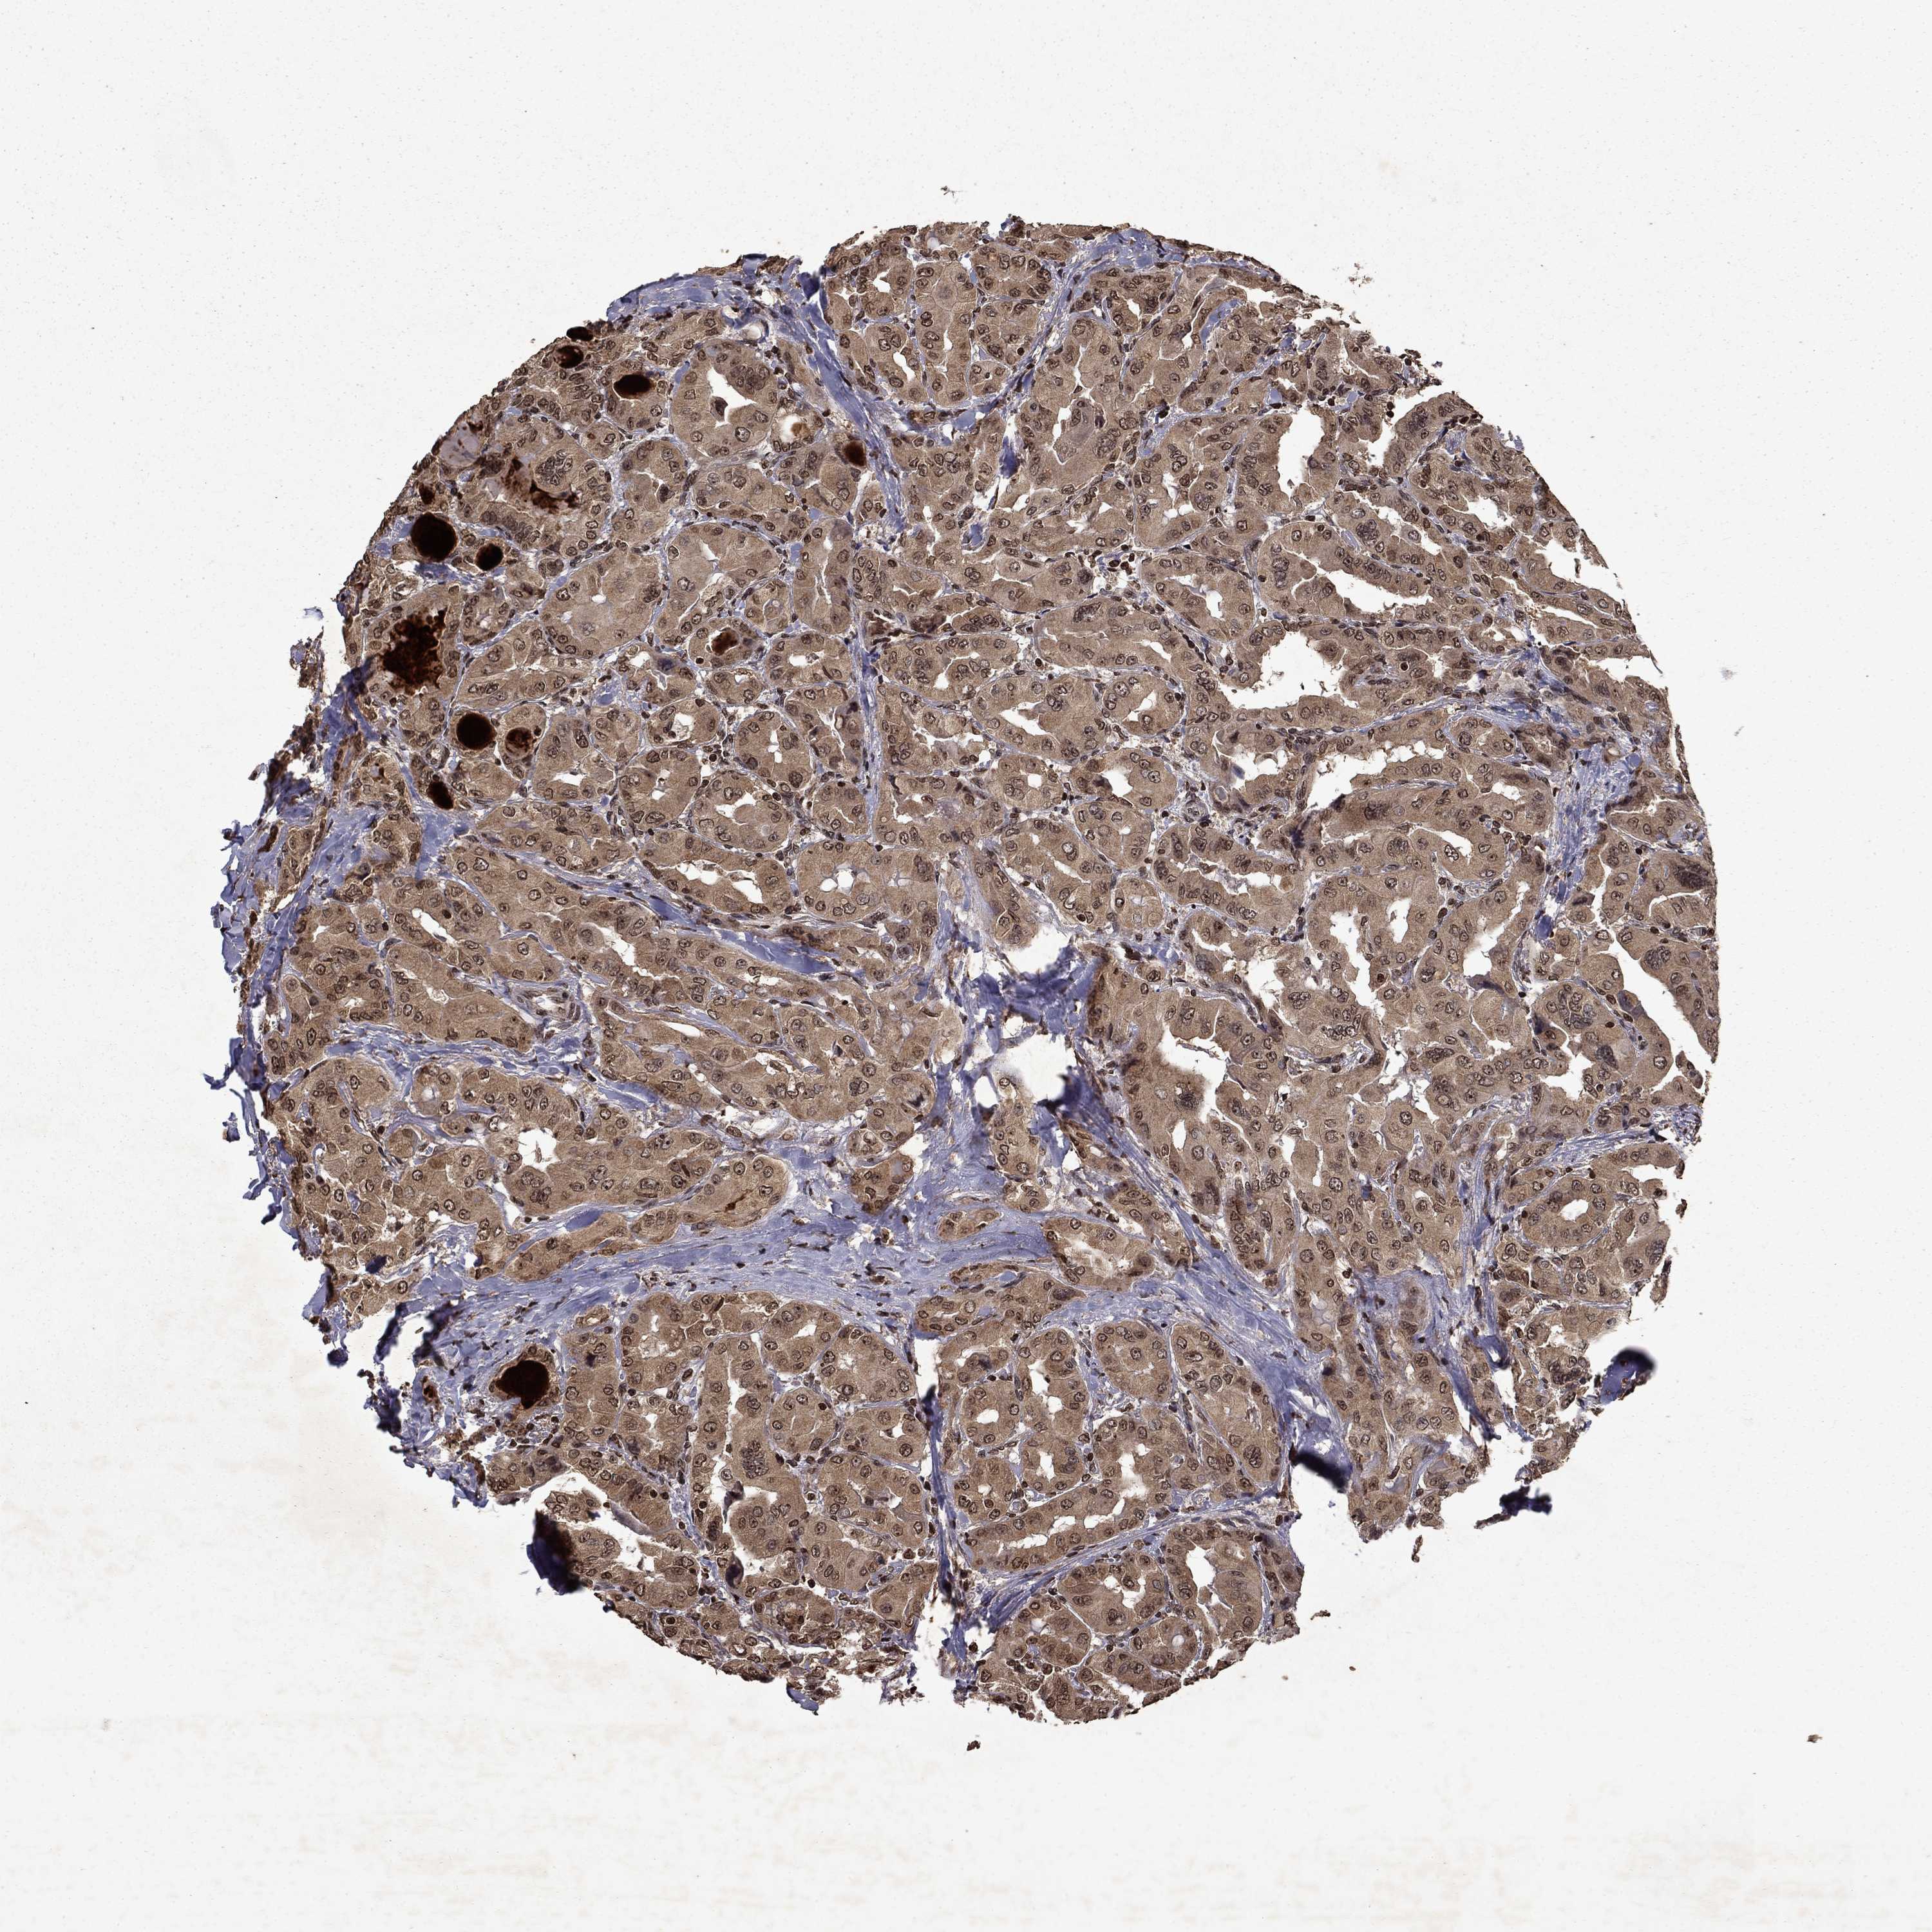

THYROID CANCER - Protein expressioni

A mouse-over function shows sample information and annotation data. Click on an image to view it in a full screen mode. Samples can be filtered based on level of antibody staining by selecting one or several of the following categories: high, medium, low and not detected. The assay and annotation is described here.

Note that samples used for immunohistochemistry by the Human Protein Atlas do not correspond to samples in the TCGA dataset.

Antibody stainingi

Antibody staining in the annotated cell types in the current human tissue is reported as not detected, low, medium, or high, based on conventional immunohistochemistry profiling in selected tissues. This score is based on the combination of the staining intensity and fraction of stained cells.

Each image is clickable and will lead to virtual microscopy that enables deeper exploration of all samples and also displays staining intensity scores, fraction scores and subcellular localization as well as patient and tissue information for each sample.

Antibody HPA054483

Antibody HPA064504

Staining

High

Medium

Low

Not detected

Intensity

Strong

Moderate

Weak

Negative

Quantity

>75%

75%-25%

<25%

None

Location

Nuclear

Cytoplasmic/membranous

Cytoplasmic/membranous,nuclear

Papillary adenocarcinoma, NOS

Follicular adenoma carcinoma, NOS